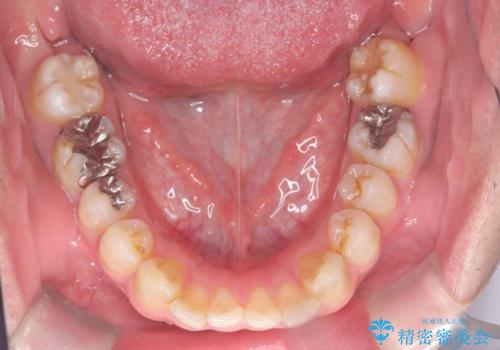

- 前歯の隙間と歯のデコボコを主訴にご来院された患者様です。

加えて、上下の奥歯が全く咬み合わないシザーズバイトの状態も認められました。

矯正検査の結果、非抜歯でインビザラインによる治療が可能と判断し、治療を行いました。